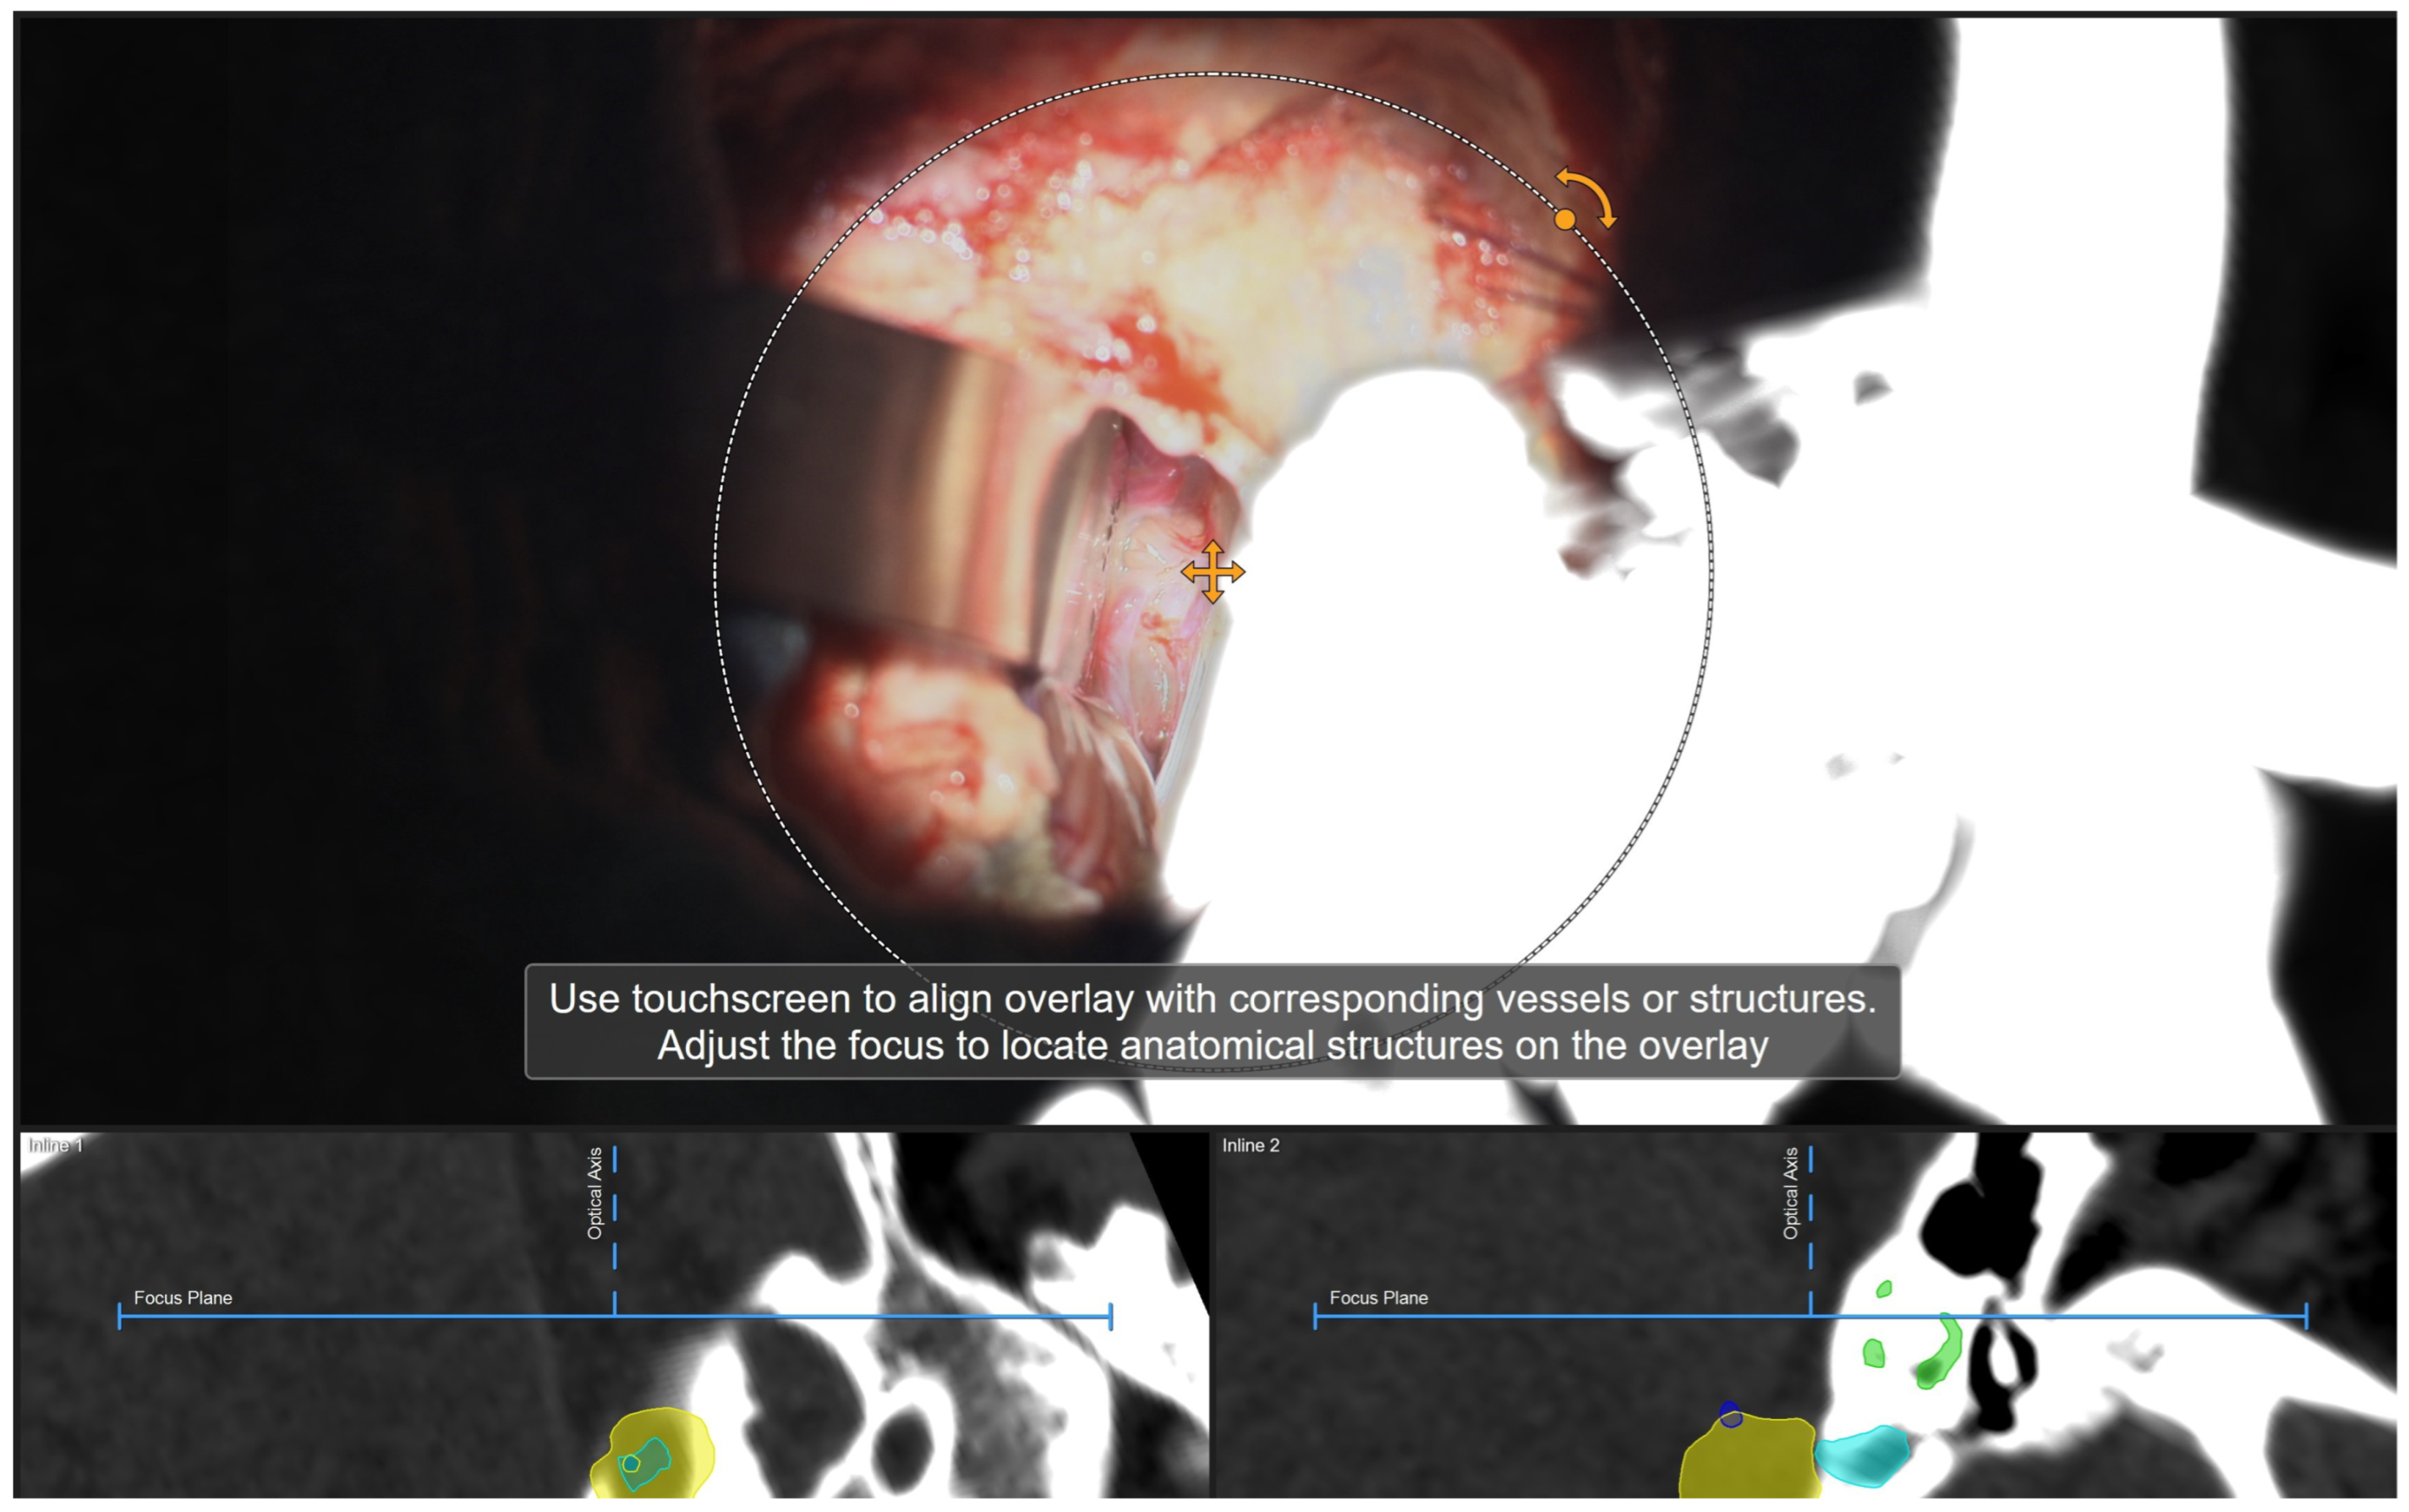

Illustrative Cases